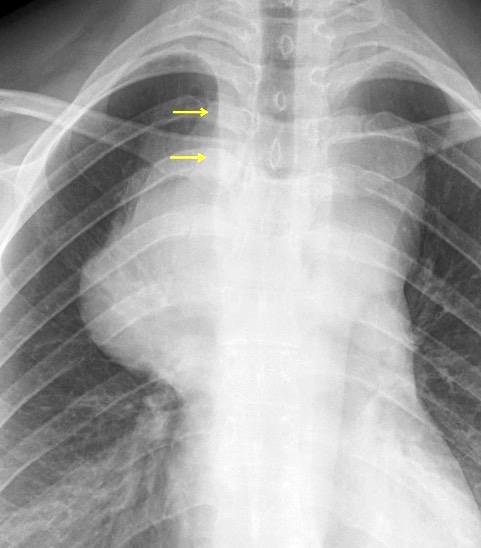

La densidad aumentada con desplazamiento lateral de la VCS es el signo más fiable

Adenopatías > 15 mm. (98 pacientes)

Ensanchamiento de la banda paratraqueal........35%

Aumento del ganglio de la ácigos.......................42%

Convexidad lateral de la VCS.................................47%

Densidad aumentada en la zona de la VCS.........83%

Müller NL. et al. Radiology 1985